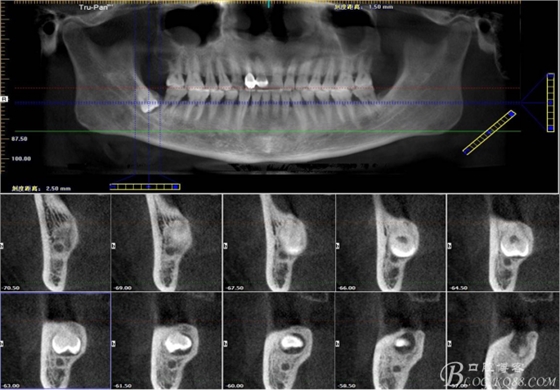

二、術(shù)前CBCT影像:

圖1.47牙冠的近中面緊鄰下頜神經(jīng)管

圖2.判斷47牙根是否吸收